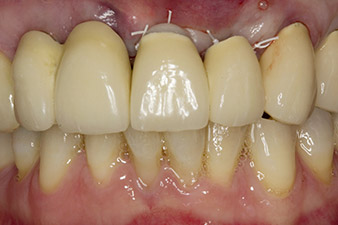

Abb. 1: Der radiologische Ausgangsbefund zeigt eine erneuerungsbedürftige verblockte Kronenversorgung. Beim Abnehmen werden die Zähne 21 und 22 unbeabsichtigt extrahiert.

Bei der Erstvorstellung sind die Zähne 21, 22 und 23 mit 19 Jahre alten verblockten Kronen versorgt. Sie sind über ein Geschiebe mit Implantaten an den Positionen 12/11 verbunden (vgl. Abb. 2). Das Röntgenbild zeigt einen horizontalen Knochenverlust um die Zähne 21 und 22 (Abb. 1).